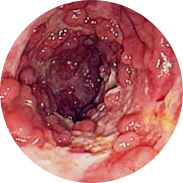

Upala i suppuracija sluznice rektuma

Krvarenje može dovesti do anemije

Povećanje tjelesne temperature, s jakom upalom, može dovesti do vrućice.

A najgora stvar je rak rektuma! Opsežna klinička ispitivanja Hemorena provedena su u Hrvatskom medicinskom centru (Zagreb) 2016. godine. Ukupno je u istraživanjima sudjelovalo više od 1000 muškaraca i žena s hemoroidima različitog stupnja. Svi ispitanici koristili su Hemoren kremu 3 tjedna. Čak su i liječnici bili zapanjeni rezultatima studije!

Više od 95% muškaraca i 98% žena primijetilo je značajna poboljšanja u roku od nekoliko dana nakon što su počeli koristiti Hemoren kremu, više od 90% sudionika u potpunosti se oporavilo od postojeće bolesti. Niti jedan od trenutno postojećih proizvoda za liječenje hemoroida nema tako visoku stopu učinkovitosti!